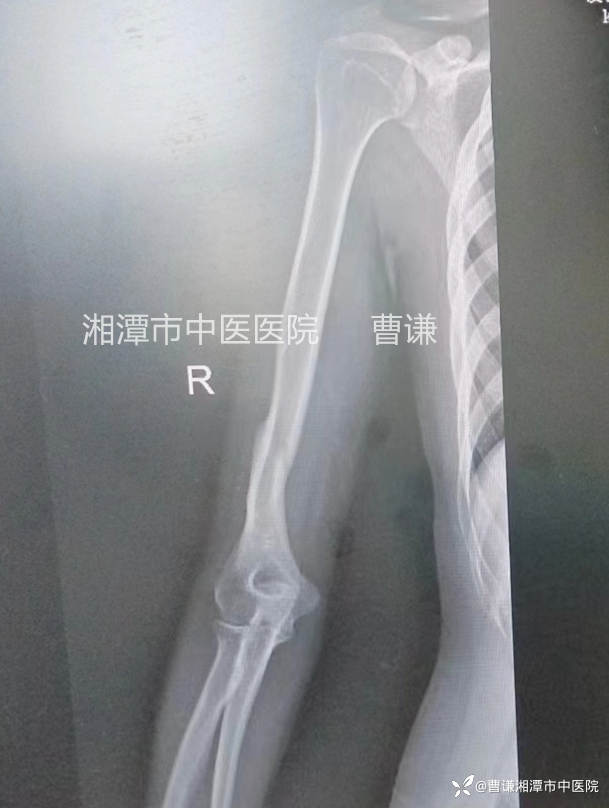

外伤后当地医院拍片情况显示右肱骨中下段骨折

入院后值班医生予以杨氏三步复位法手法复位(具体手法参看——肱骨中上段粉碎骨折的保守治疗)小夹板外固定,拍片复查示骨折对线良好,断端稍有分离,请我阅片后,我认为目前对位对线情况不影响预后,可以继续维持,指导患者积极进行握拳伸掌功能锻炼。